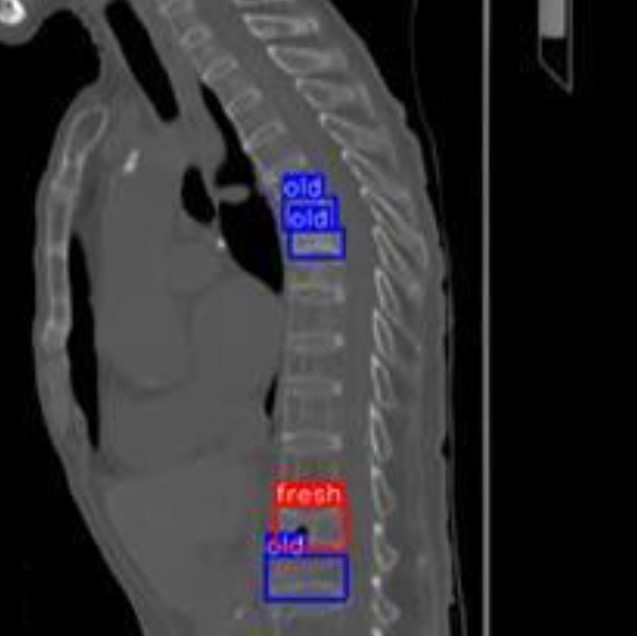

嘉義大林慈濟醫院與雲林科技大學今天發表成功開發CT影像AI判讀系統,有效區分骨折新舊狀態,準確率高達93.4%,該研究2024年10月刊登於國際SCI期刊。圖/大林慈濟醫院提供

嘉義大林慈濟醫院與雲林科技大學今天發表成功開發CT影像AI判讀系統,有效區分骨折新舊狀態,圖為檢測結果。圖/大林慈濟醫院提供

研究團隊蒐集大林慈濟醫院1萬305張脊椎CT影像,選用5631張側面切面影像進行AI訓練與測試,導入YOLOR深度學習架構,並結合3種影像特徵模型(MobileViT、EfficientNet_NS與CSPDarknet53)與Involution技術進行優化,最後透過集成學習方式整合各模型優勢,成功建立準確率高達93.4%的AI系統。